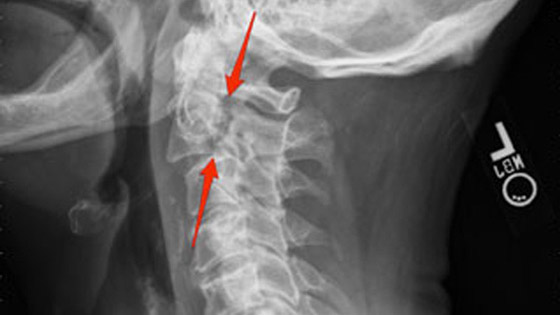

مكان اصابة النخاع الشوكي

اصابة النخاع الشوكي